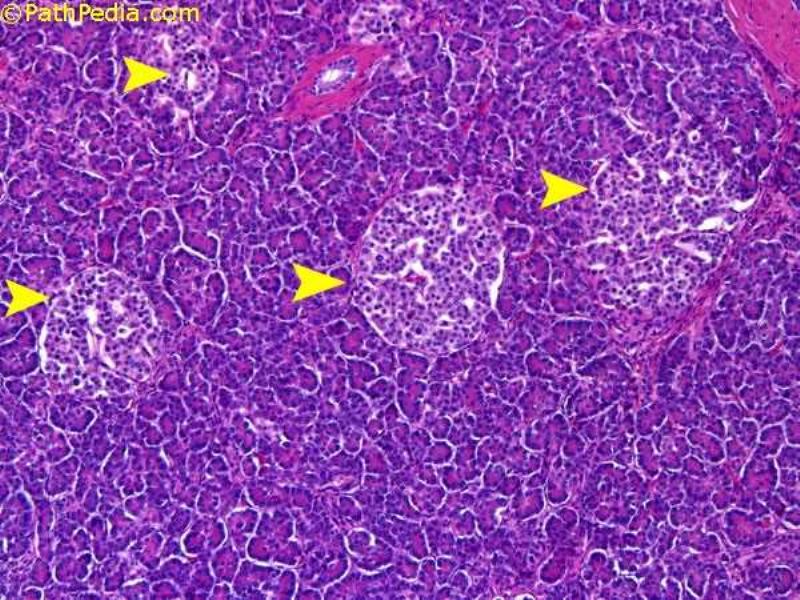

Slide 50 - Pancreas

- Exocrine + Endocrine

- Acinar / Tubulo-acinar

- Simple epithelium of pyramidal serous cells

- Basal basophilia

- Duct starts inside acinus

- Centro-acinar cells

- Endocrine islands